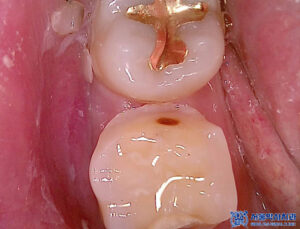

확인 결과,

오른쪽 위·아래 치아에

충치가 진행되어 있었고,

이로 인해 치주염과 치수염까지

동반된 상태였습니다.

먼저 충치를 제거하였습니다.

충치가 비교적 깊은 위치까지

진행되어 있었으며,

그 영향으로 치아 뿌리 끝까지

염증이 퍼진 상태로 확인되었습니다.

또한 같이 치료하기로 했던

다른 치아들은 충치 제거 후

확인해 보니,

많이 깊지 않아 신경치료 없이

크라운으로 마무리 하기로 하였습니다.